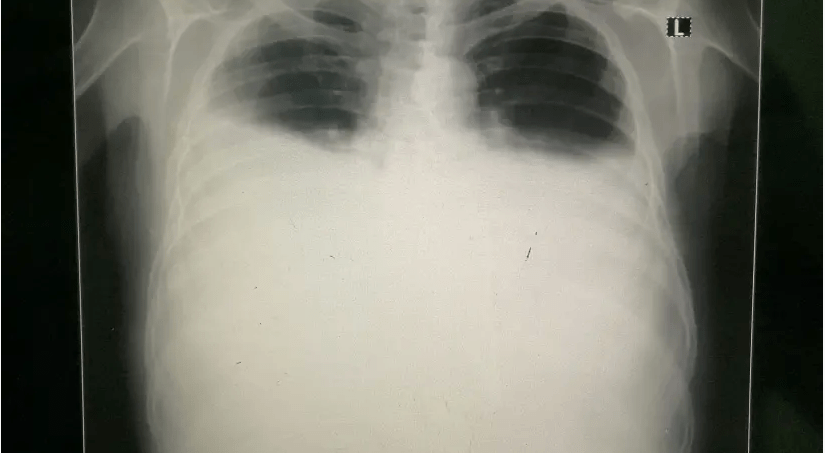

La solution d'imagerie identifie automatiquement les résultats suggérant un épanchement pleural à partir des scanners CR, DR et DX.

Cette solution permet de recevoir les résultats suggérant un épanchement pleural à partir des scanners CR, DR et DX, avertissant rapidement les radiologues et leur permettant à la fois de traiter et de prioriser efficacement les cas urgents.

Aux États-Unis, environ 1,5 million de personnes reçoivent chaque année un diagnostic d'épanchement pleural, une accumulation de liquide entre les couches de tissu qui tapissent les poumons et la cavité thoracique.

Le plus souvent causés par une insuffisance cardiaque congestive, une infection pleurale et une tumeur maligne, près d'un tiers des patients atteints d'épanchement pleural meurent dans l'année suivant leur hospitalisation.